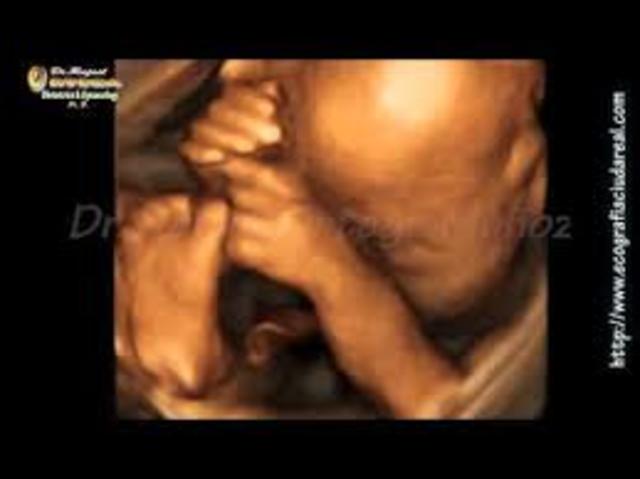

Hola Mamá, tu bebé está cada vez más desarrollado, sus sentidos están cada vez más agudos, durante todas estas semanas ha aprendido a moverse para estar más cómodo, ya sabe en qué posturas está mejor, por tanto será normal que sientas que se mueve más y al estirarse y buscar su postura favorita te dará más de una patada.